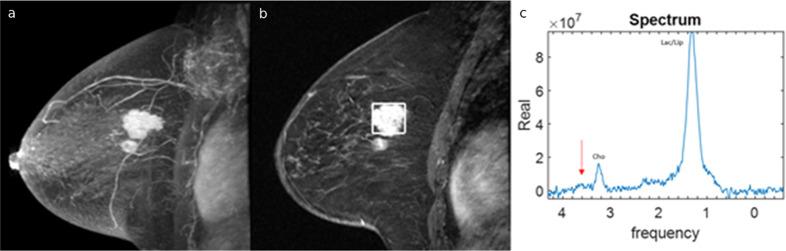

Magnetic resonance spectroscopy (MRS) is a promising non-invasive diagnostic method that can detect and quantify endogenous tissue metabolites. High glycine levels obtained from breast MRS have been associated with poor prognosis; however, glycine evaluation has not been reported regarding MRS. We report our finding in a breast cancer patient in whom pre-treatment but not post-treatment MRS showed elevated glycine and discuss the implications of this finding.

磁共振波谱(MRS)是一种很有前景的非侵入性诊断方法,它可以检测和定量内源性组织代谢物。乳腺MRS检测到的高甘氨酸水平与预后不良有关;然而,关于MRS的甘氨酸评估尚未见报道。我们报告了一名乳腺癌患者的发现,该患者治疗前而非治疗后的MRS显示甘氨酸水平升高,并讨论了这一发现的意义。